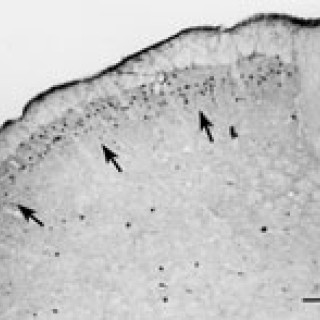

Artikkelen er tidligere publisert i Ugeskrift for Læger 2002; 164: 1334 – 8 Tabel 1 Fedtindhold i modermælk, modermælkserstatning og komælk per 100 ml (1) Modermælk Modermælkserstatning Komælk (sød) Total fedt (g) 4,2 3,6 3,5 Mættet fedt (g) 1,9 1,7 2,3 Monoumættet fedt (g) 1,5 1,2 0,9 Polyumættet fedt (g) 0,6 0,5 0,1 Transfedtsyrer (g) 0,1 0,1 0,1 Kolesterol (mg) 16 0 14 Udviklingen af aterosklerose er en livslang multifaktoriel proces. Forståelsen af de tidlige processer i denne udvikling er øget væsentligt de seneste år. Under indtryk af sammenhængen mellem hjerte-kar-sygdom og kostvaner...